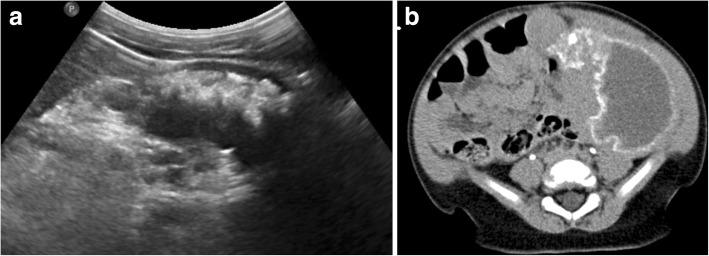

戈谢病是一种遗传性代谢紊乱疾病,会导致溶酶体酶β-葡萄糖脑苷脂酶缺乏,进而引起多个器官内异常巨噬细胞(“戈谢细胞”)的蓄积,最明显的是影响肝脏、脾脏和骨髓。作为最常见的糖脂代谢紊乱疾病,对于接触这些患者的放射科医生而言,熟悉器官和骨髓受累的影像学进展并了解影像学在临床决策中的作用非常重要。近期出现了可用于测量脂肪分数的商用、可靠且可重复的定量MRI采集方法,这促使人们重新审视骨髓受累定量评估的作用。本文综述了戈谢病的各种影像学表现,并讨论了用于确定实体器官和骨髓受累情况的更优化定量方法,重点是包括弹性成像在内的其他定量方法的未来应用。